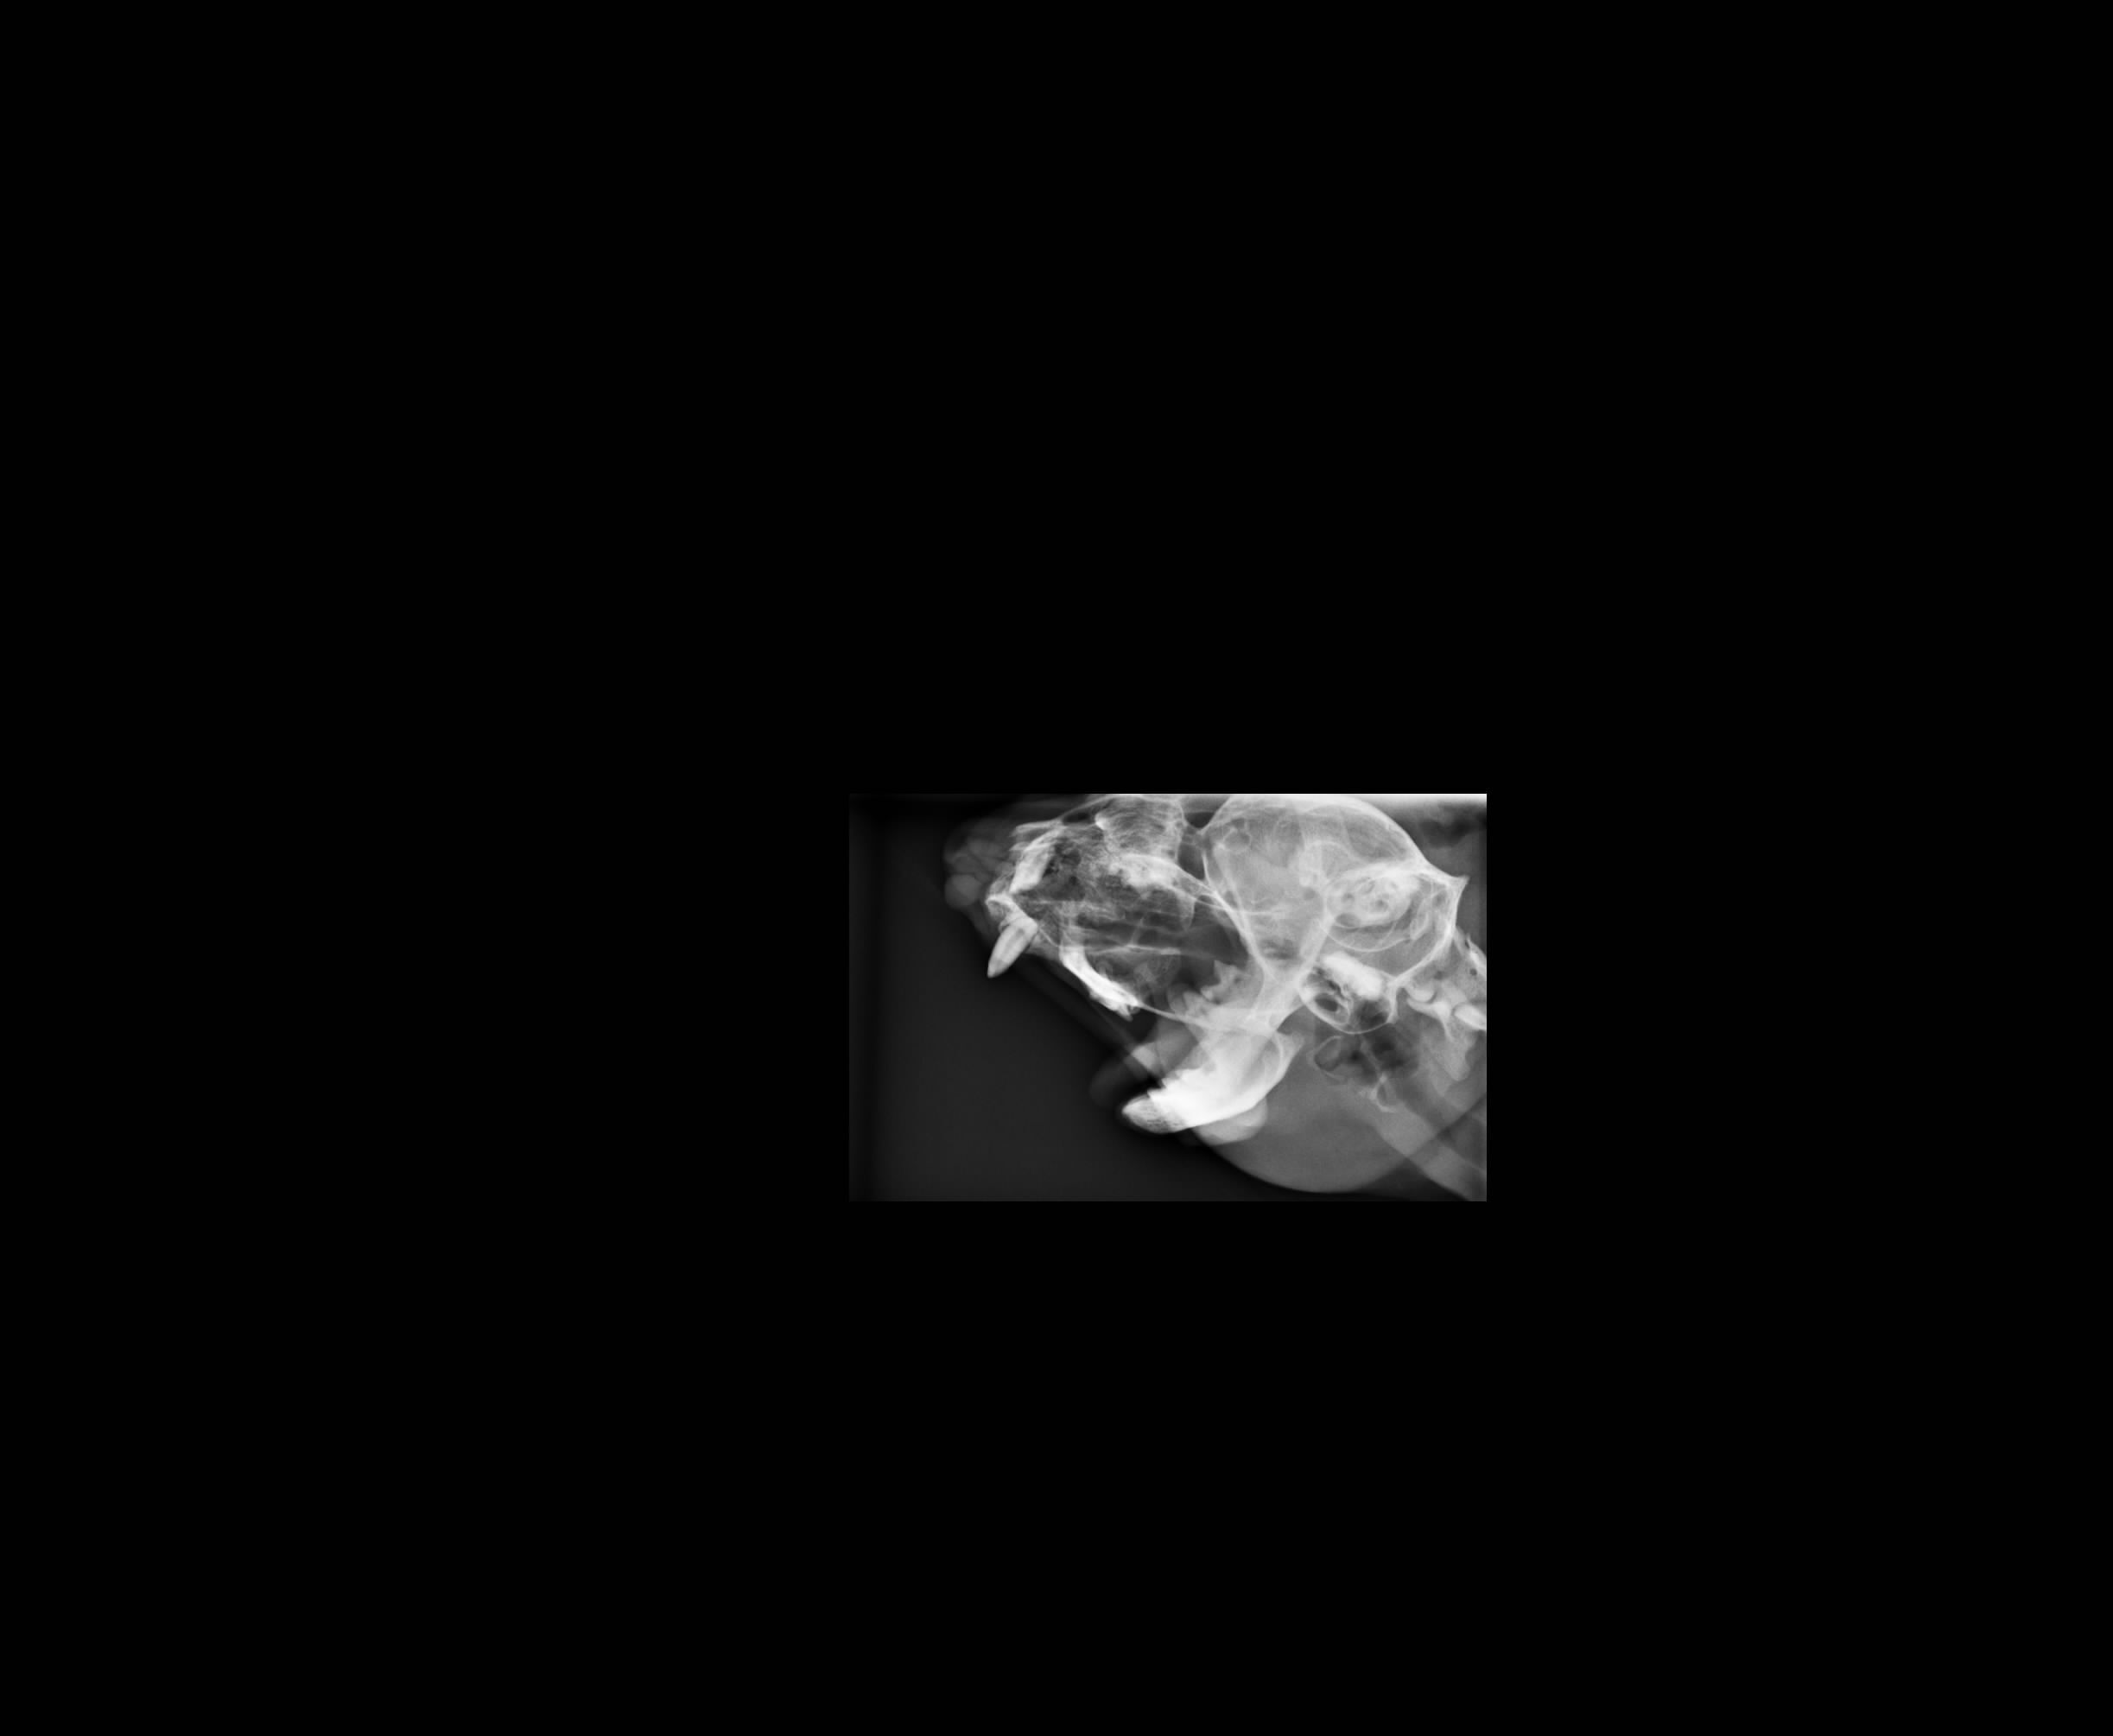

經過醫生細心檢查後發現,

貓咪本身是未絕育公貓,僅2.95kg

消瘦.疑似下巴有傷,

故從這一方面著手治療~

經過X光片檢查

發現下巴的皮膚與牙齒是呈現分離的~

但不影響到進食的問題....

1.X-ray 400*4